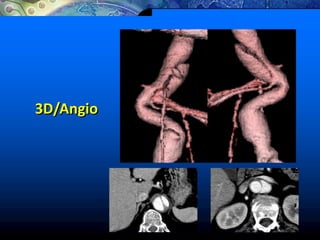

3D/Angio